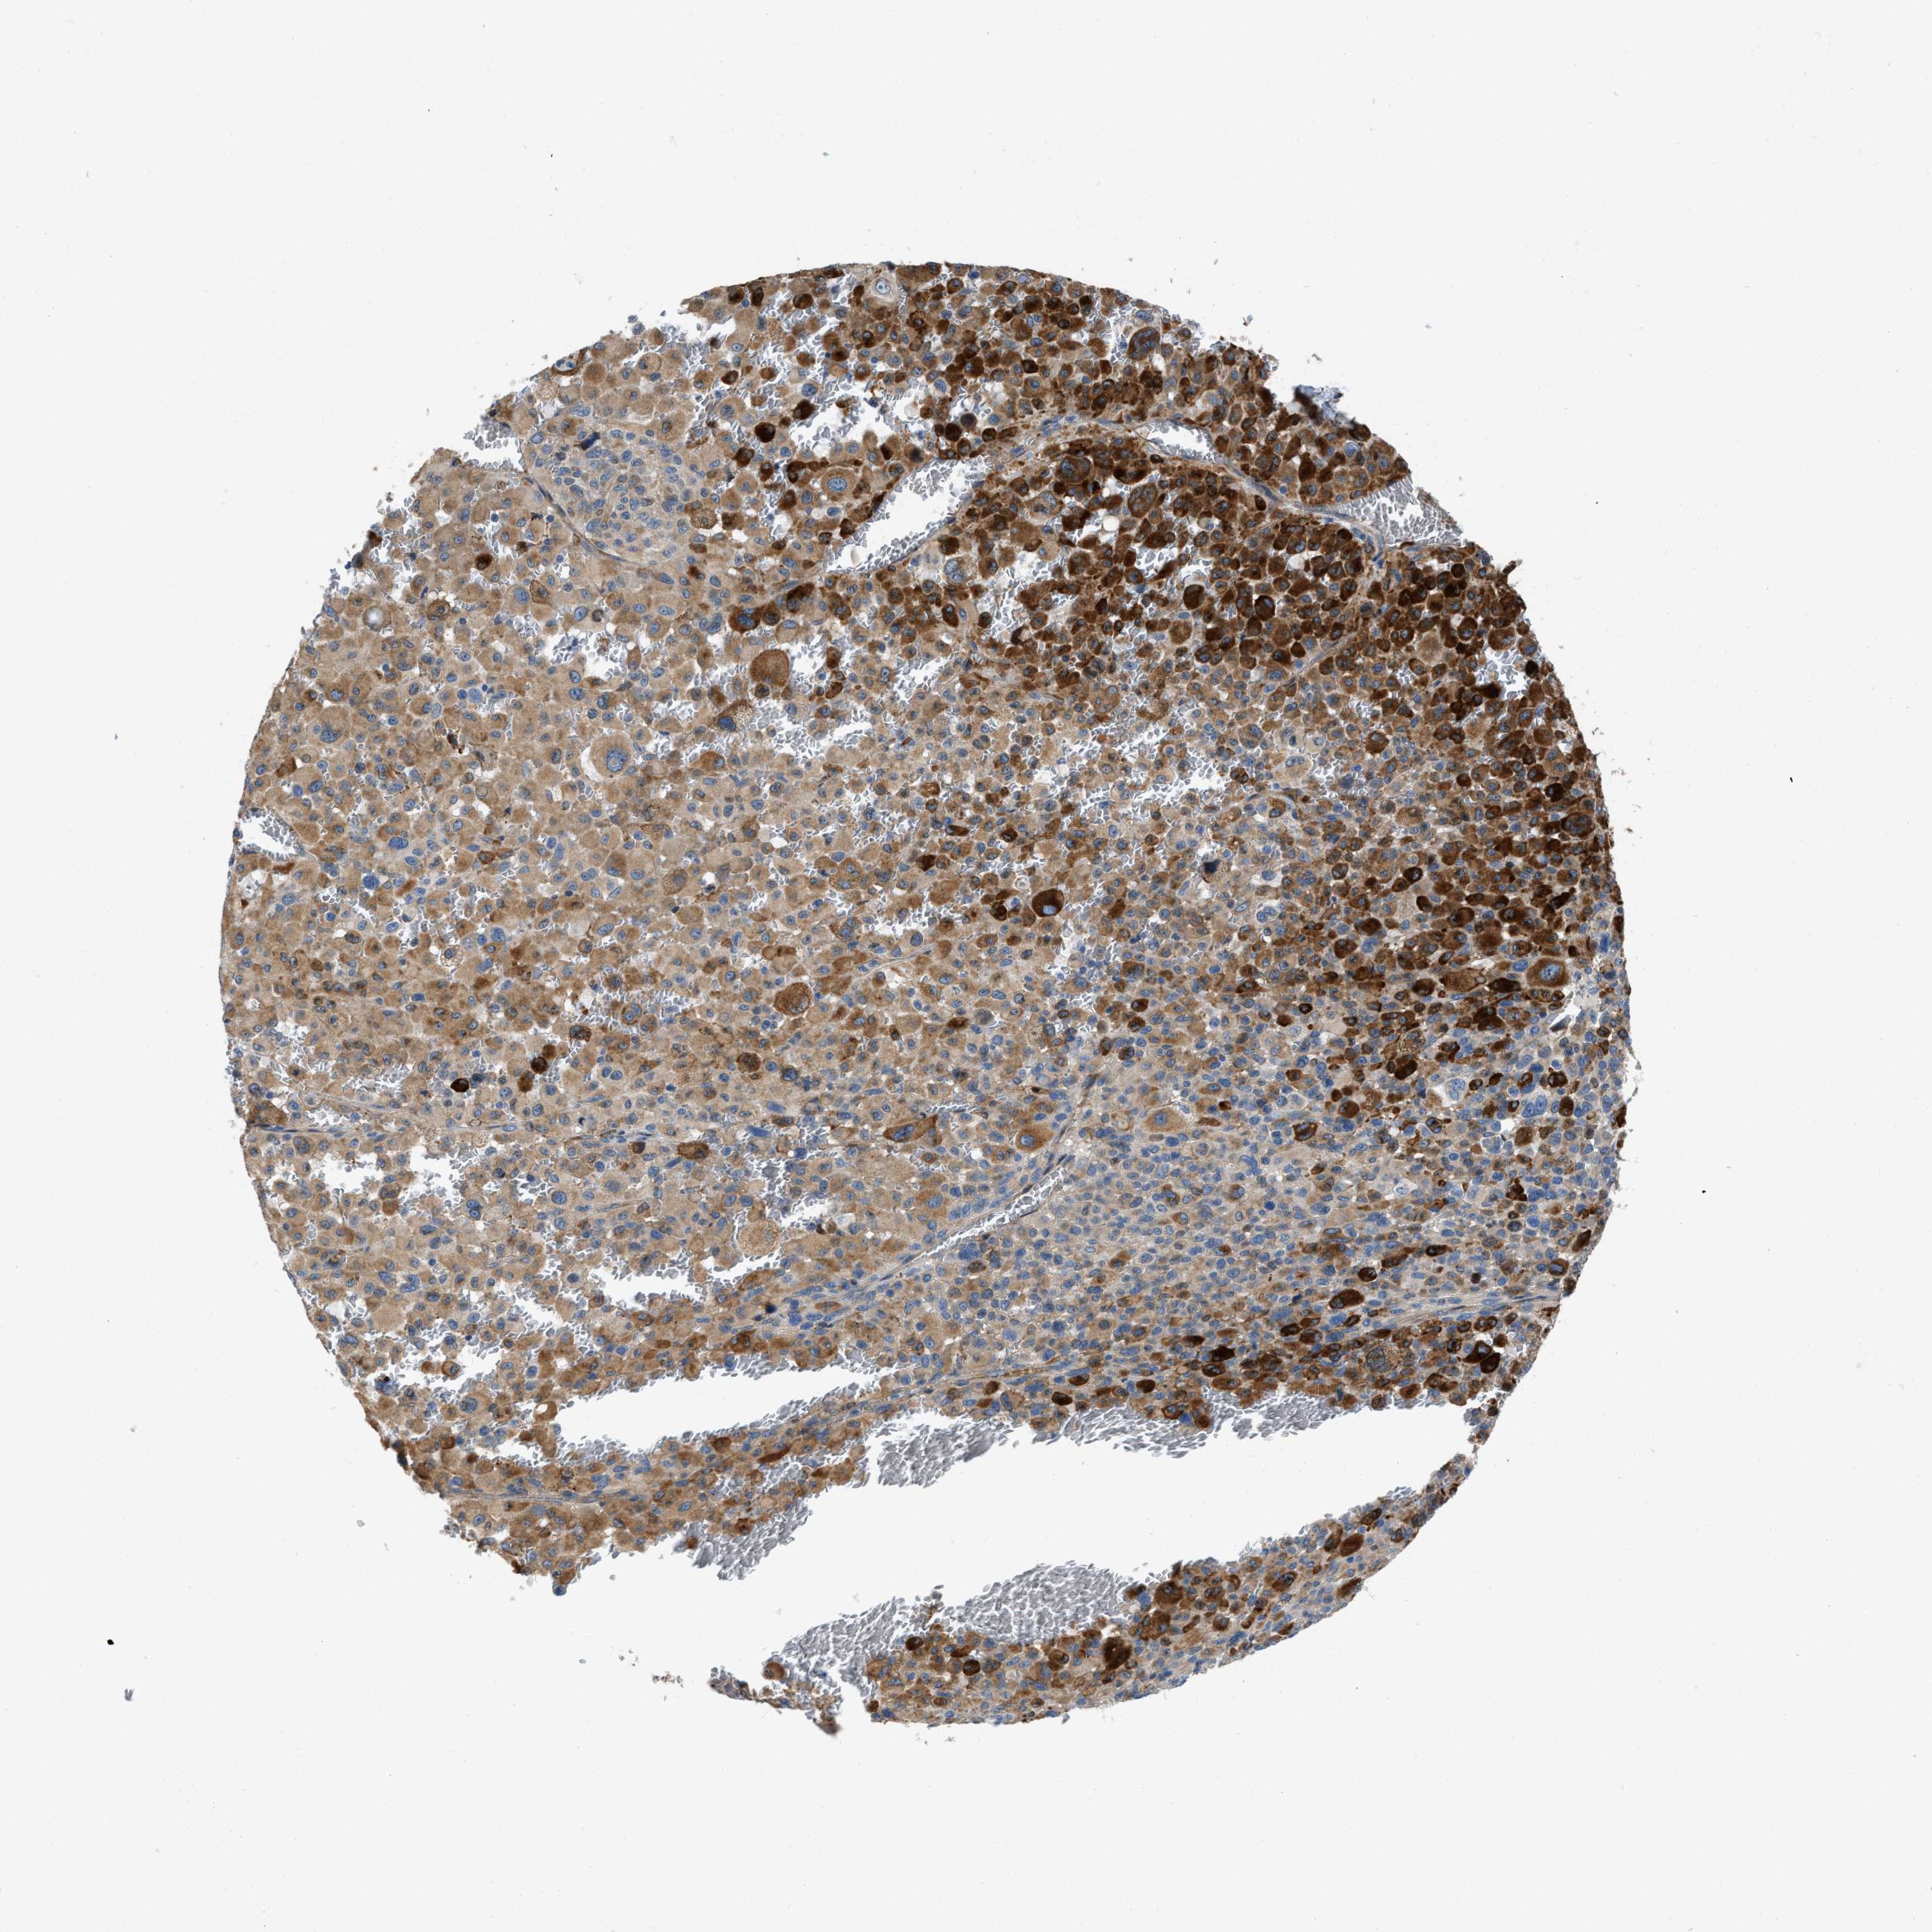

MELANOMA - Protein expressioni

A mouse-over function shows sample information and annotation data. Click on an image to view it in a full screen mode. Samples can be filtered based on level of antibody staining by selecting one or several of the following categories: high, medium, low and not detected. The assay and annotation is described here.

Note that samples used for immunohistochemistry by the Human Protein Atlas do not correspond to samples in the TCGA dataset.

Antibody stainingi

Antibody staining in the annotated cell types in the current human tissue is reported as not detected, low, medium, or high, based on conventional immunohistochemistry profiling in selected tissues. This score is based on the combination of the staining intensity and fraction of stained cells.

Each image is clickable and will lead to virtual microscopy that enables deeper exploration of all samples and also displays staining intensity scores, fraction scores and subcellular localization as well as patient and tissue information for each sample.

Antibody HPA018284

Staining

High

Medium

Low

Not detected

Intensity

Strong

Moderate

Weak

Negative

Quantity

>75%

75%-25%

<25%

None

Location

Nuclear

Cytoplasmic/membranous

Cytoplasmic/membranous,nuclear

Malignant melanoma, NOS

Malignant melanoma, Metastatic site